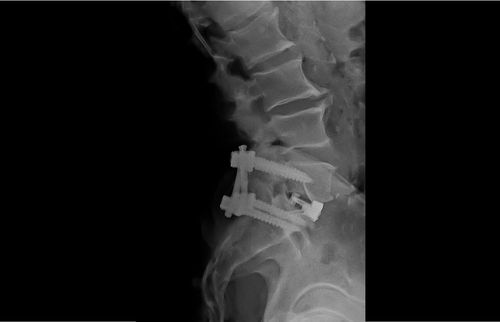

TLIF

Posterolateral Fusion